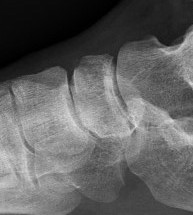

CT

Minimally displaced navicular stress fracture

Displaced navicular stress fracture